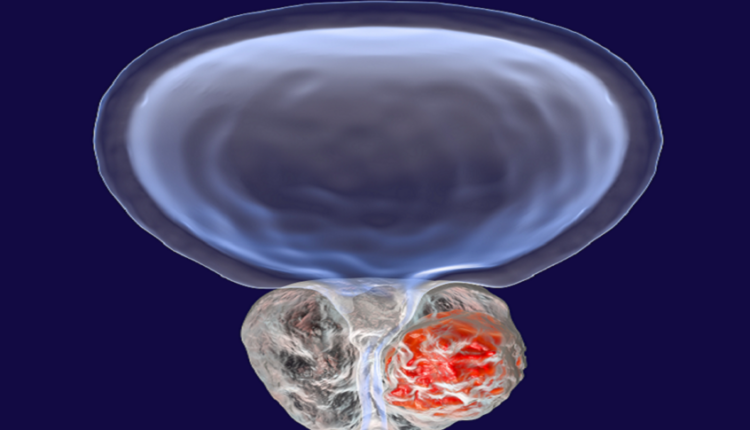

أعلن باحثون في الجامعة الوطنية الروسية للبحوث عن اكتشاف علمي جديد يكشف آلية غير متوقعة لعمل جزيئات الحمض النووي الريبوزي الميكروي، ما قد يفتح آفاقا جديدة لفهم تطور سرطان البروستاتا وتشخيصه مبكرا.

كما أظهرت الدراسة أن هذه الأشكال المختلفة من الجزيء قادرة على تثبيط نشاط نحو 50 جينا بكفاءة عالية، وهو ما يفسر ارتباطه القوي بتسارع نمو سرطان البروستاتا وبعض الأورام الخبيثة الأخرى، الأمر الذي يعزز فرضية استخدامه كمؤشر حيوي لتطور المرض.

كما تشير تقديرات الصندوق العالمي لبحوث السرطان إلى أن سرطان البروستاتا يعد ثاني أكثر أنواع السرطان شيوعا عالميا، حيث يتم تشخيص نحو 1.46 مليون حالة سنويا، مع تسجيل قرابة 397 ألف حالة وفاة، وغالبا ما يصيب الرجال في سن متقدمة.